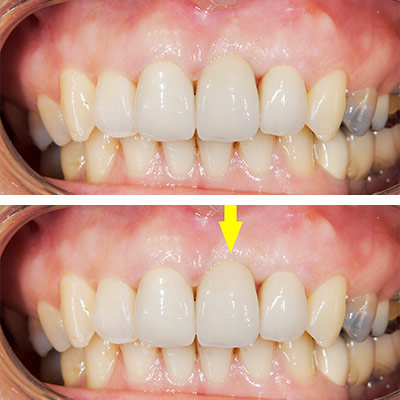

例えば、-

上顎前歯2本のうち向かって右の歯がインプラントなのですが、歯肉がわずかに上にあがってしまい、全くの左右対称にはできずに、右の歯の方が少し長くなってしまっています。

-

もう少し長くなっていますが、口唇を上に引っ張らない限りはそれが見えません。

一見それほど問題にならない程度には仕上がっていますが、隣の歯との間、歯肉の間に空間が残っており、中にはご満足いただけないこともあります。幸いにして、この患者様方には、あらかじめ、見た目についてのご説明をさせていただいた上で、治療を始めていますので、ご納得いただいております。

審美性をさらに高め、天然歯とまったく区別ができない様にしようと思えば、追加の費用をいただいて、歯肉の移植術を行なうなど、方法はありますが、その患者様のお考えになるレベルが様々で、ご満足いただけない場合もあり、当院では、非常に高度な審美性はお約束できないと、ご説明させていただいています。